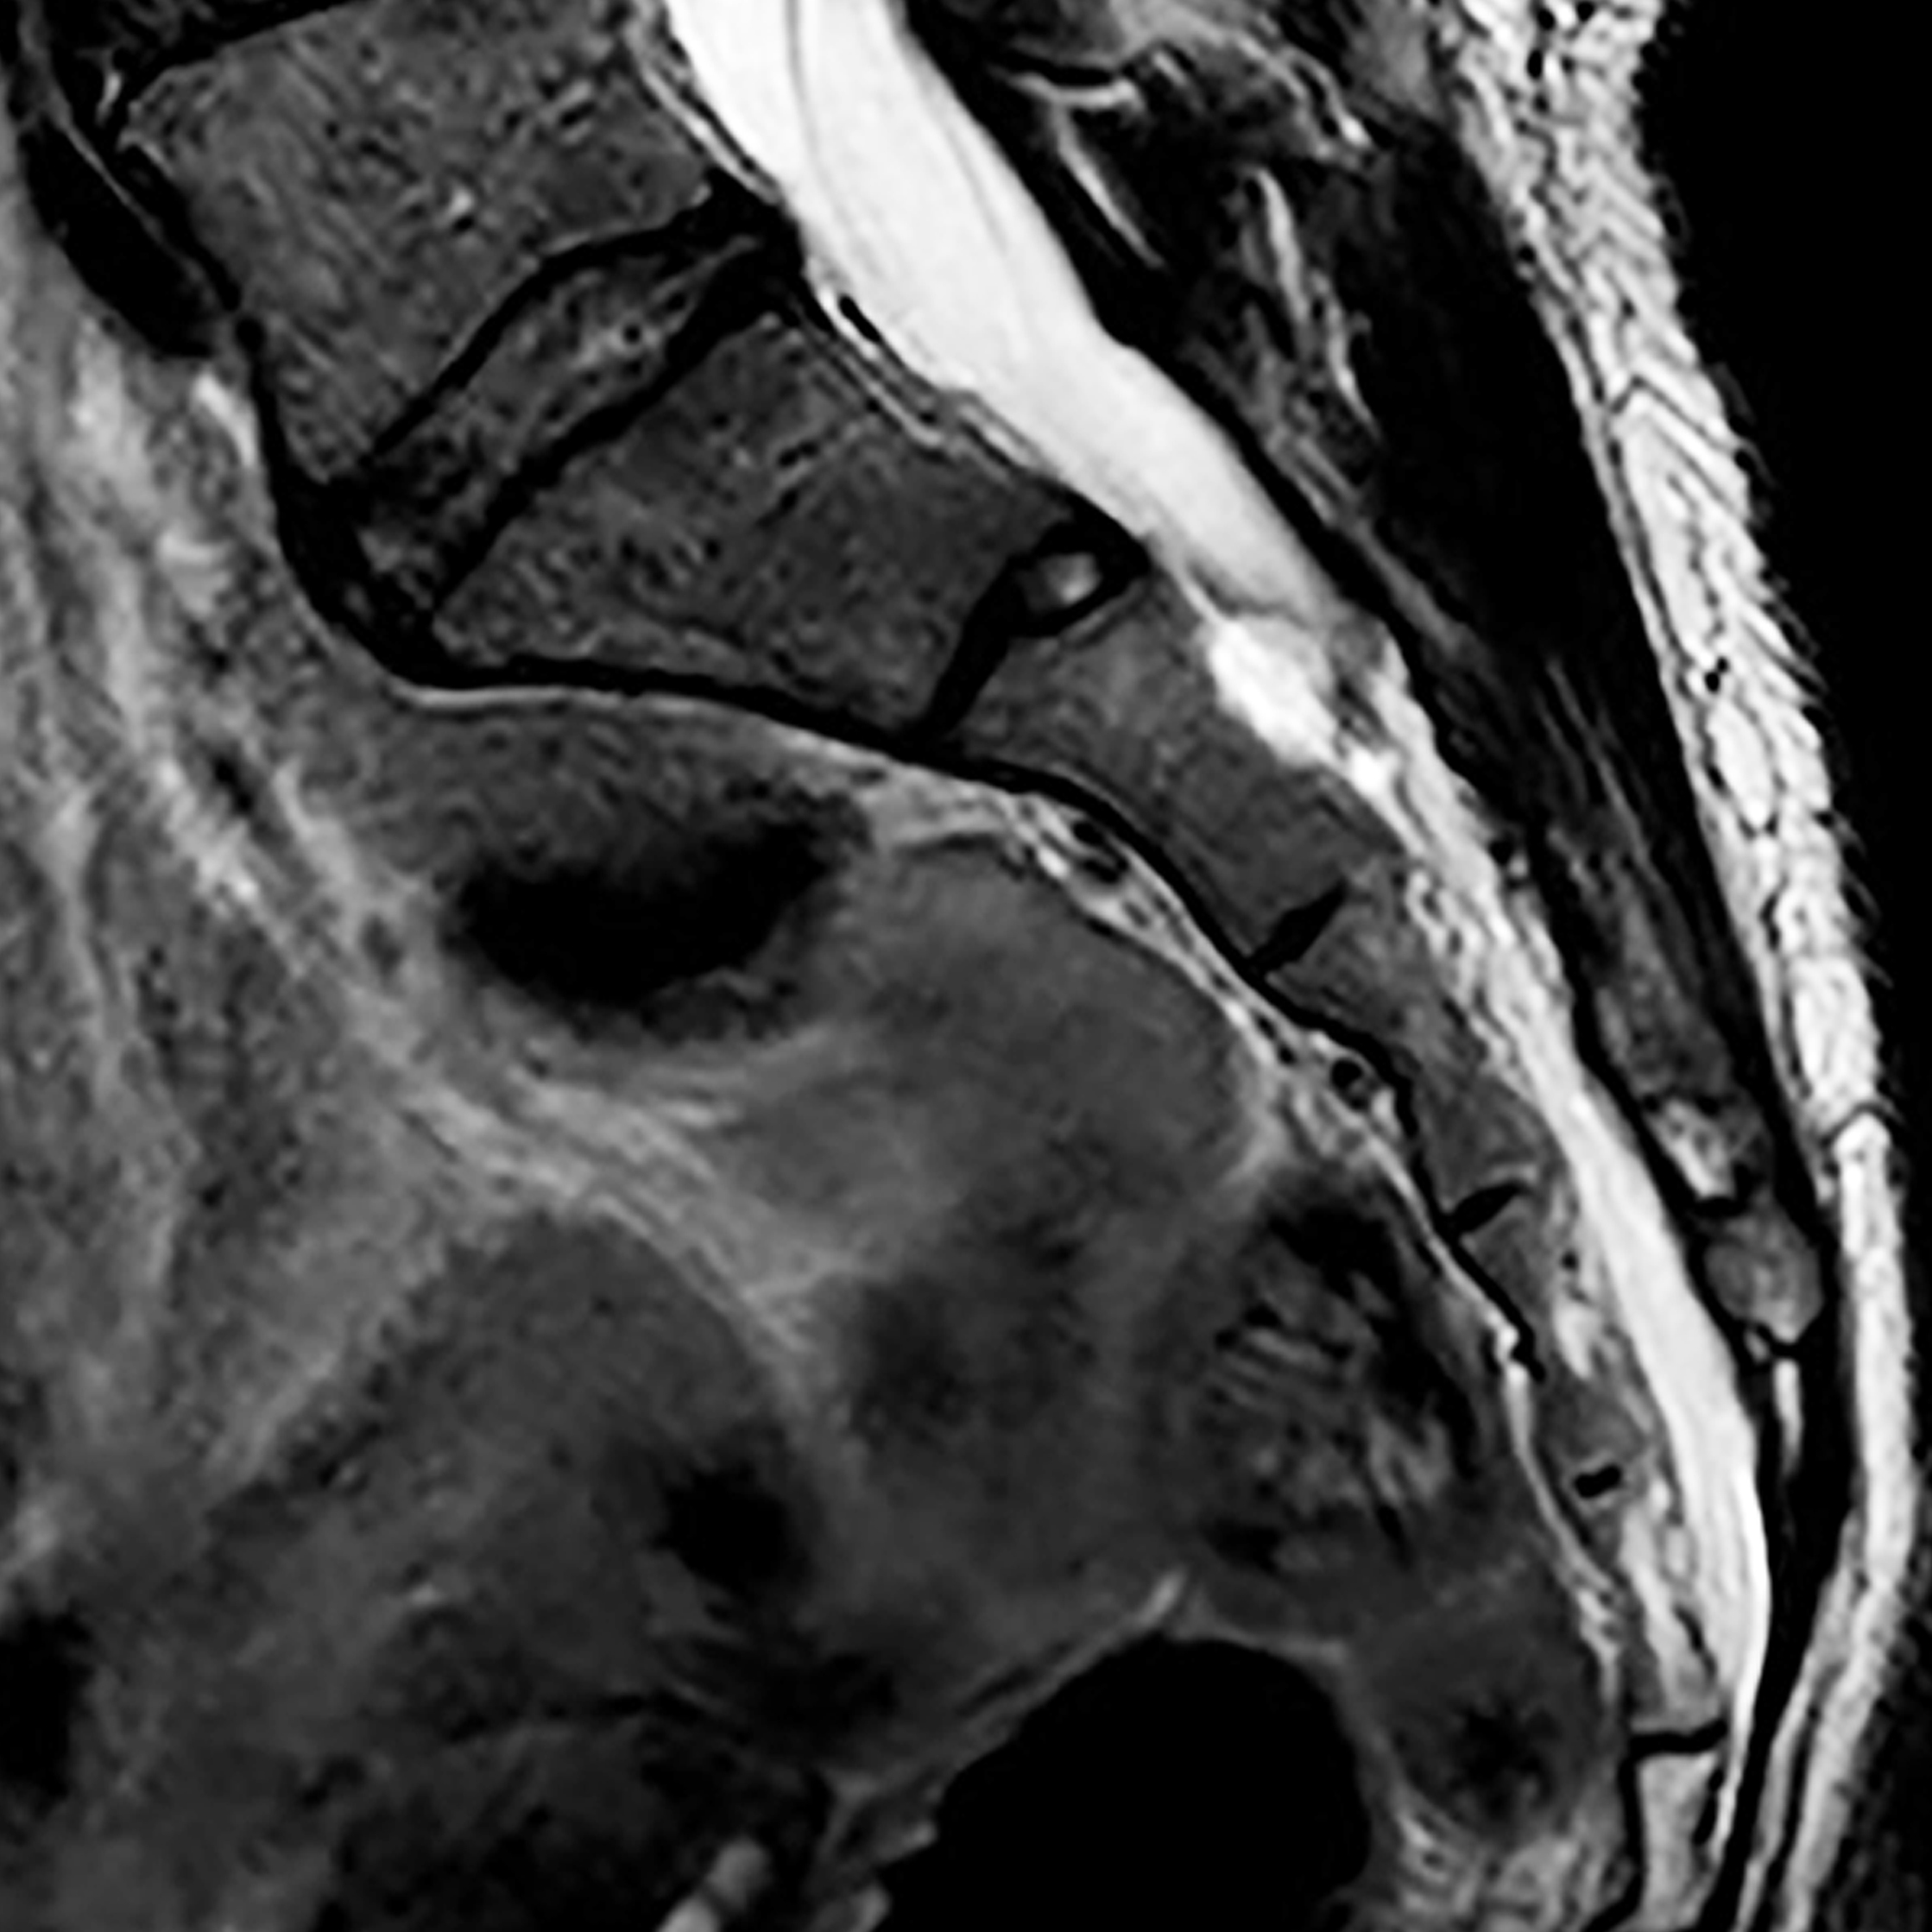

Ho pensato di presentare questo progetto attraverso un percorso di narrazione che si arricchisce progressivamente di contenuti e di presenze. Lo spazio maggiormente coinvolto è la vetrina di Mesia Space dove verrà proiettato inizialmente il lungometraggio omonimo Stone, un video della durata di circa 5 ore. In seguito, sempre all’interno della vetrina, il video sarà sostituito da un’installazione tridimensionale costituita da un gruppo di immagini della risonanza magnetica della mia colonna vertebrale, stampate su un tessuto di nylon semitrasparente. L’installazione nella vetrina rimarrà per tutta la durata del mio intervento a Mesia. La performance invece si svolgerà nello studio adiacente e consiste in un incontro di psicoterapia, di circa 50 minuti. Una psicoterapeuta si occuperà del mio vissuto, condividendo con me un ulteriore percorso di cura ampliato dalla funzione di testimonianza dei presenti. La seduta sarà documentata da un video che sarà proiettato il giorno del finissage.